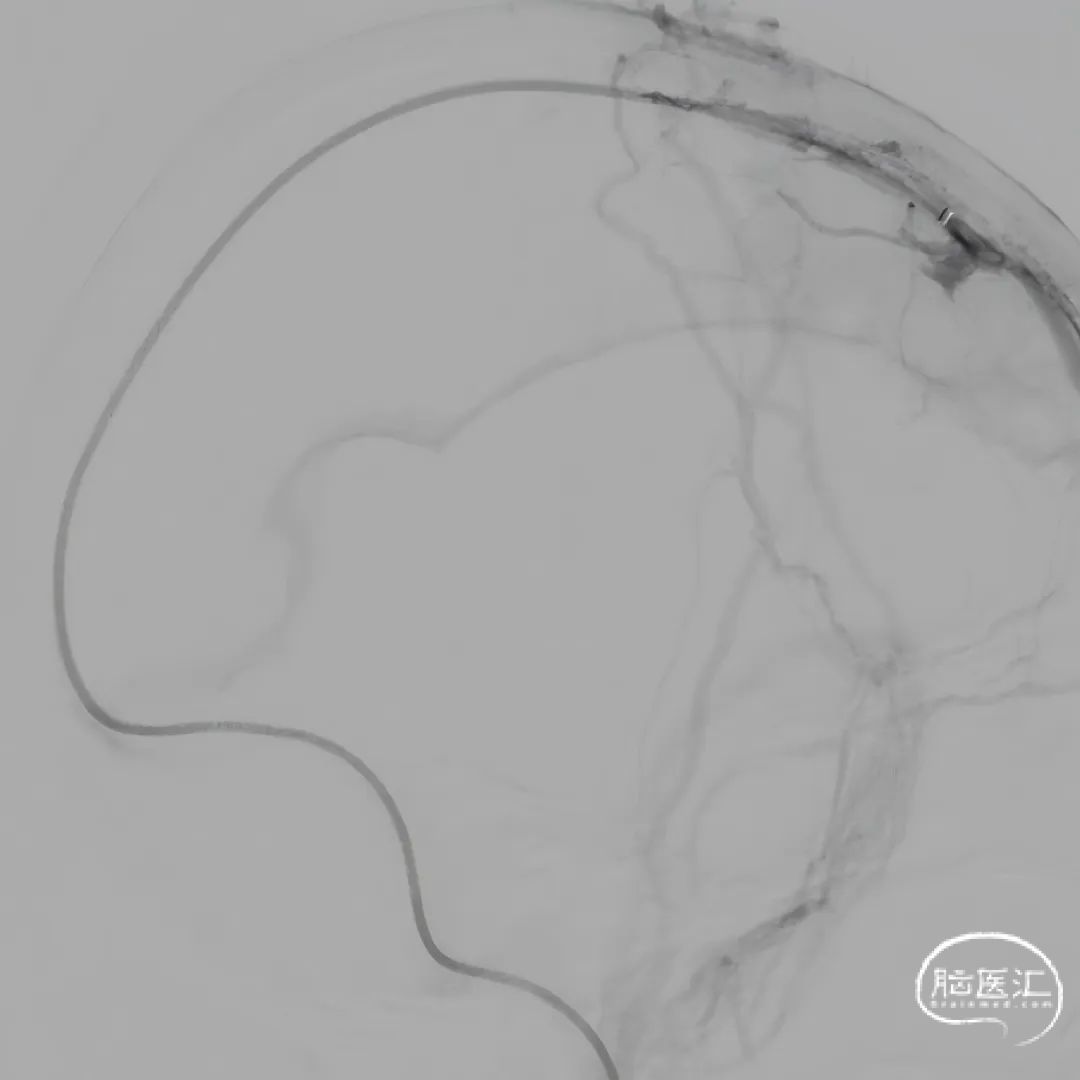

股动脉穿刺置5F鞘做静脉窦造影,股静脉穿刺置8F鞘进行治疗。260cm泥鳅导丝,将132cm 0.068" React™导管送至上矢状窦前部,尽量推高长鞘,增加支撑力。

经中间管手推造影,确认血栓位置。

球囊扩张和接触溶栓后,再次经中间管反复抽吸后复查造影。

再次给予尿激酶10万U后复查造影。

再次给予球囊扩张,球扩后复查造影。